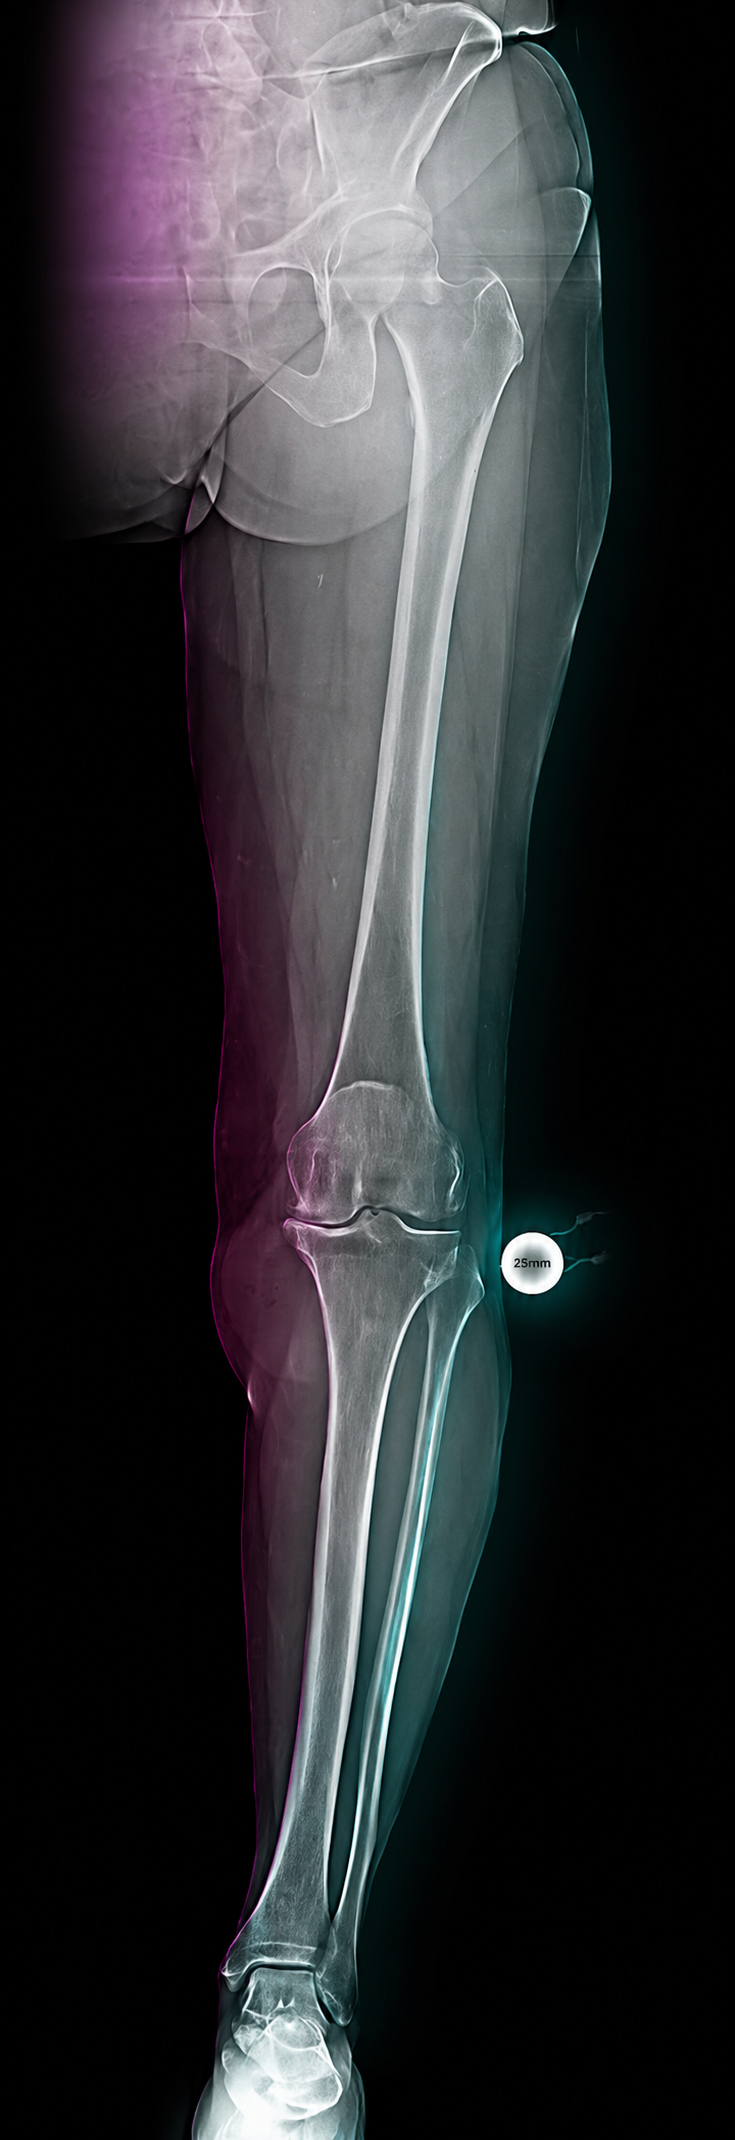

A compact guide for radiology teams on correct calibration sphere placement in orthopedic X-ray imaging. The marker must be positioned in the anatomical plane of the target joint so that digital scaling, measurements and preoperative templating remain clinically reliable.